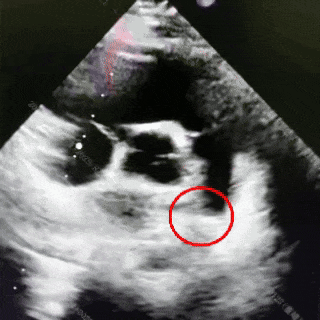

术后3个月随访

可见封堵器形态良好,无残余分流